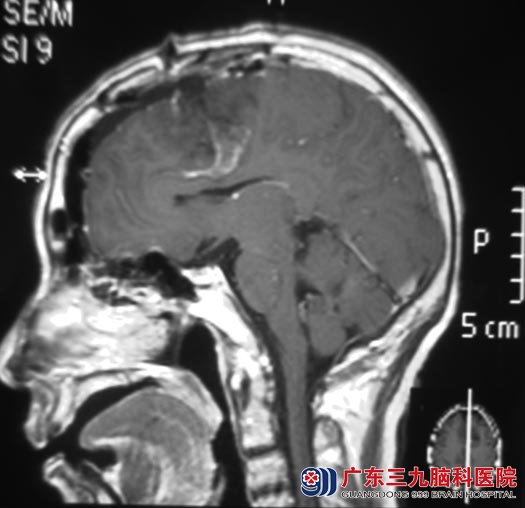

在广东三九脑科医院进一步检查,头颅MR检查提示:左额部占位,大小约5.0cm×3.8cm×4.8cm。得知自己的颅内有肿瘤,李阿姨吓得茶饭不思,以泪洗脸。

广东三九脑科医院综合神经外科 鲁明主任参考影像资料,初步考虑为脑膜瘤。